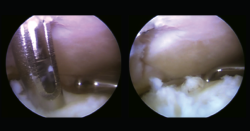

Figura 4. Acceso artroscópico a través de la sindesmosis a la lesión osteocondral. Nanoperforaciones. Se observa lesión condral inestable con lengüeta de base medial.

En un segundo tiempo se realizó un portal de trabajo mediante acceso transindesmótico anterior a 4 cm desde la línea tibioastragalina (Figura 3), previa disección roma en la piel, valorando la accesibilidad desde este punto de entrada a la lesión osteocondral previamente con una aguja de venopunción de 21 G × 1 1/2” (0,8 × 40 mm) y una vez localizado el punto de entrada con aguja de Kirschner de 1,5 mm de diámetro. Posteriormente, se realizaron nanoperforaciones en el hueso subcondral (Figura 4), reinserción del cartílago con implante reabsorbible de copolímero poliláctico (SmartNail®, ConMed Linvatec, Largo, FL) (Figura 5).

Figura 5. Reinserción mediante implante reabsorbible de copolímero poliláctico (SmartNail®, ConMed Linvatec, Largo, FL).